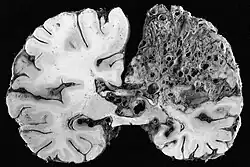

| Large arteriovenous malformation of the parietal lobe | |